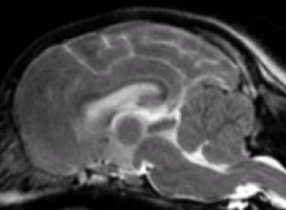

Here is a comparison of squashing/pinching of cerebellum--from

very full to very squashed.

As you look at these you can easily see

the cerebellum is more and more squashed/compressed the further down

you go. There also appears to be a

noticeable shortening of the area behind the main brain in these

particular dogs. If you look at the many MRIs on this

site, you will note that the VAST

majority of Cavaliers are within range of

the 2nd and 3rd ones.

The one at the top is extremely rare in

this breed. It appears almost normal.